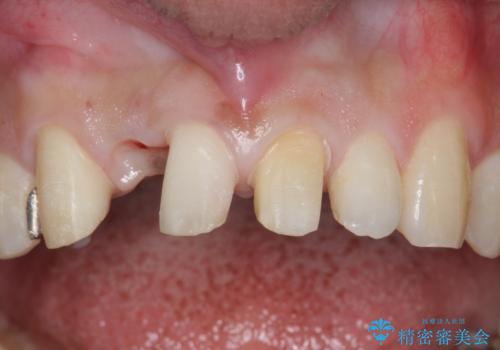

- 他院で右上の前歯の状態が悪いことを指摘されて来院。

昔ぶつけてしまった既往がありました。

歯の根の部分が内部で吸収し、周りの骨も吸収してしまっていました。

このまま放置すると、骨の吸収も進行し、いずれ近い将来歯が折れてしまう可能性もありました。また、隣の歯にも骨の吸収による影響が始まっており、持たせるだけ持たせたとしても次のステップの時には状況が悪化してしまうことが予想されました。

以上を説明したところ、早めに抜歯を行いブリッジにしていくことを希望されたため治療開始しました。

右上2番の周りの歯槽骨がかなり吸収が進んでいた影響で、抜歯後そこが大きくへこむことが予想されました。

抜歯後即時にバイオスを詰めることで抜歯後の骨の吸収をなるべく抑える治療(ソケットプリザベーション)を行いました。

歯槽骨が吸収してしまった右上1(隣の歯)との境界については右上1番遠心の歯周ポケットが深いことについては解決できない為、いずれまたダミーの歯の部分に関しては歯肉が下がってしまうことについては説明済みです。

ただ、年齢も鑑みて、直ちに右上12抜歯ではなく、まずは2番のみの抜歯でブリッジにする処置を行いました。